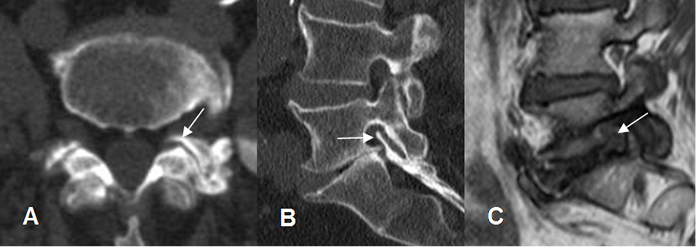

Fig 58. Canal estrecho lateral.

A: TAC axial, B: TAC reconstrucción sagital y C: RM sagital en T1. Hipertrofia de articulaciones intervertebrales y formación de osteofitos, que disminuyen la amplitud del agujero de conjunción. Hay pérdida de la grasa normal, en la RM. En B y C hay cambios degenerativos en L5-S1, con pérdida del espacio, fenómeno del vacío y deshidratación del disco.